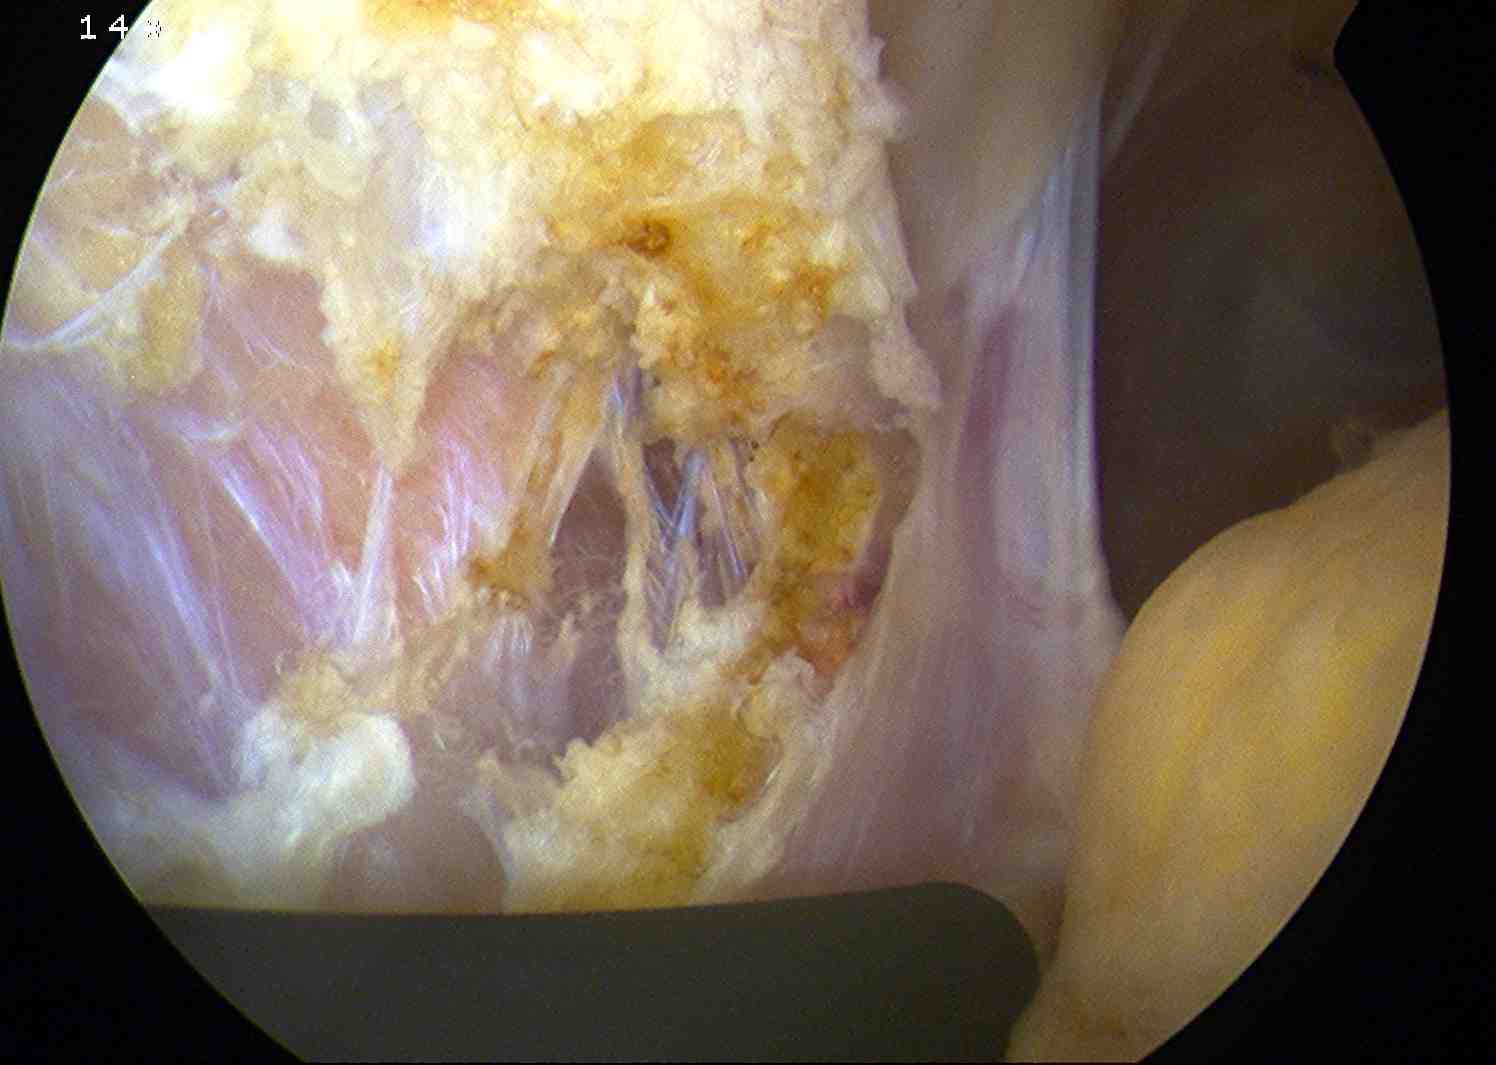

Arthroscopy

Patterns

Lateral facet - patella maltracking / trochlea dysplasia

Medial facet - patella dislocation and cartilage damage

Global - primary OA, patella fracture, obesity

Central trochlea - repetitive deep flexion

Medial facet OA Lateral facet OA